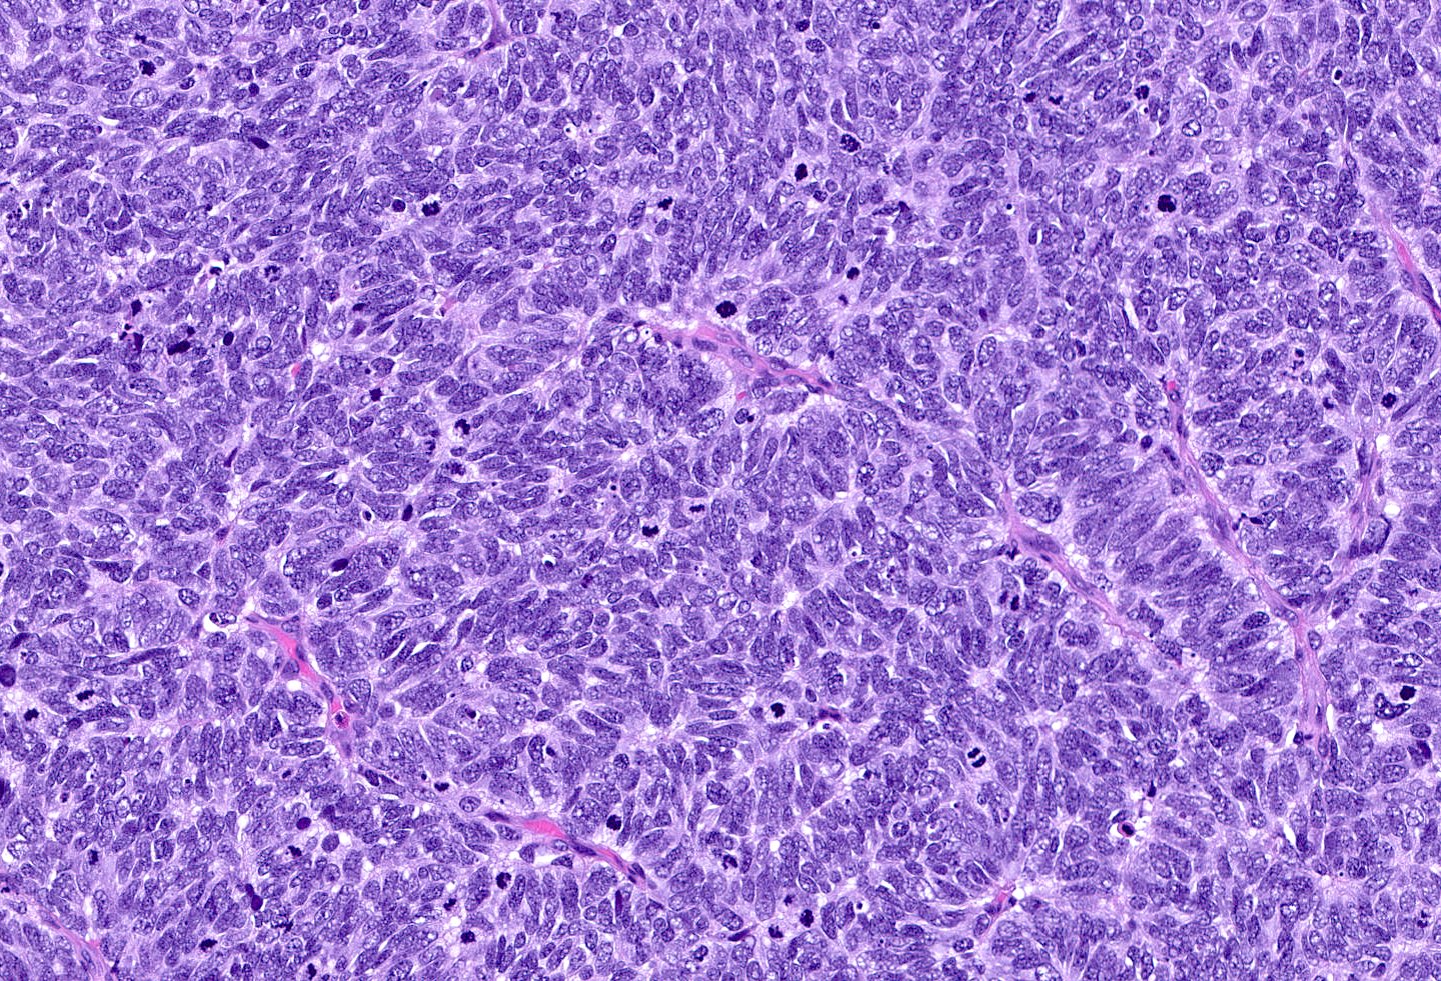

Contributed by Joshua J.X. Li, M.B.Ch.B., Gary M. Tse, M.B.B.S. and Kristen E. Muller D.O.

Large cell carcinoma

- Large cell carcinoma:

- High grade features (frequent necrosis, lymphovascular invasion and mitosis) similar to small cell carcinoma

- Tumor cells have a larger amount of cytoplasm

- Chromatin pattern coarse with occasional distinct nucleoli

- Neuroendocrine carcinomas of the breast histologically indistinguishable from their counterparts of other primaries